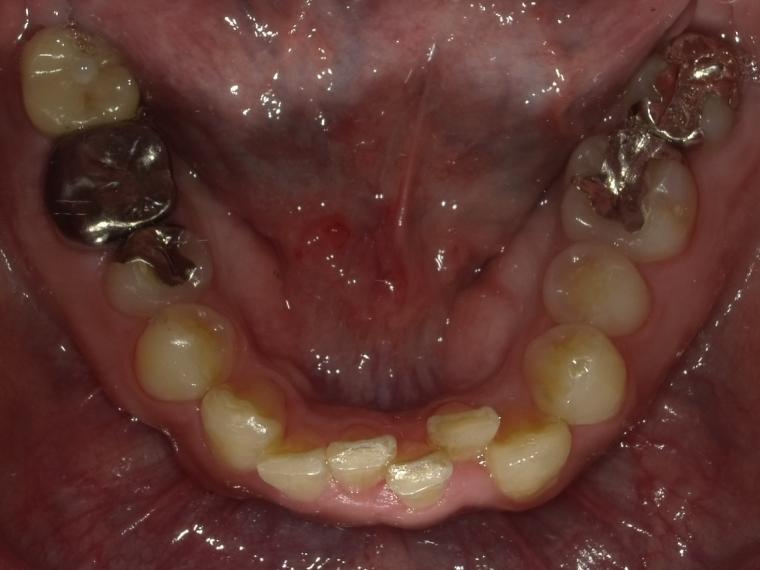

AFTER

38歳男性/下1本欠損/インプラント埋込手術

虫歯が進行していて、歯を保存出来なかったため歯を抜いて人工の骨を足してからインプラントを

1本埋込した患者さんです。

現在も定期検診で拝見させていただいてます。